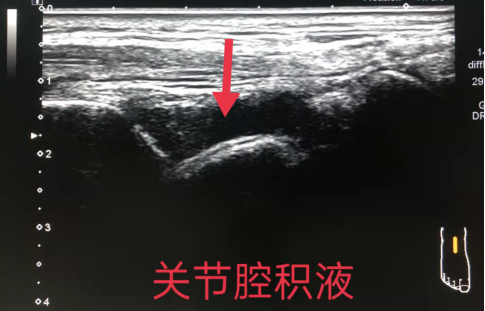

1、关节疾患:关节腔积液(血)、滑膜增厚(非特异性)、游离体、痛风性关节炎、类风湿性关节炎疗效监测、检出部分骨侵蚀、骨赘、退行性关节病(骨关节炎)等。